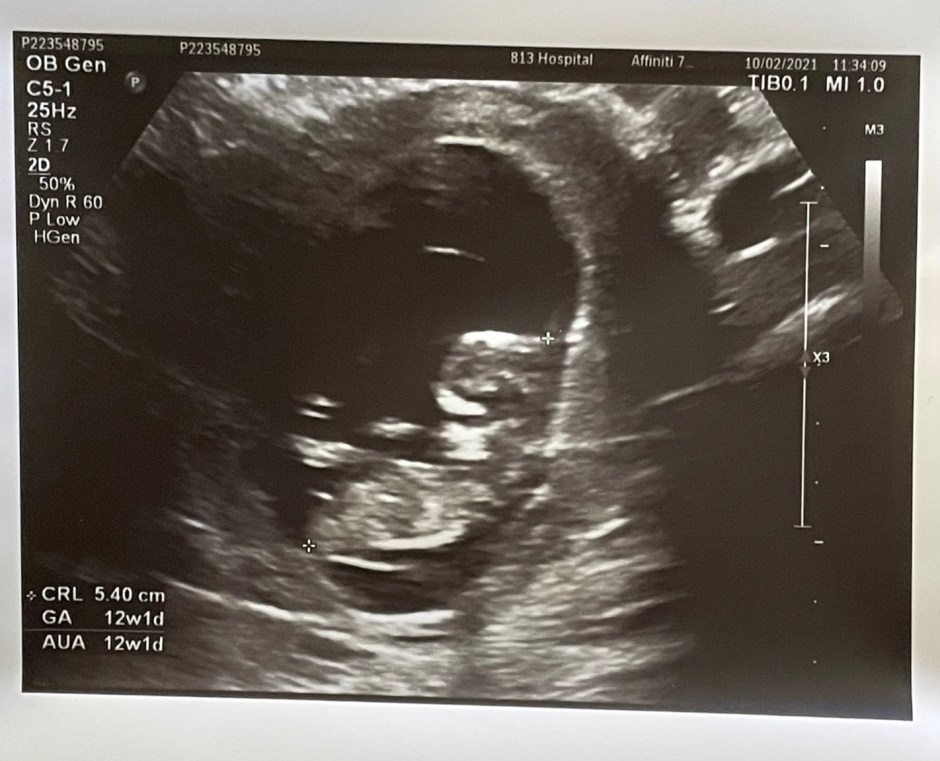

12週的超音波照已經可以看到寶寶的形狀了,醫生說羊水很充足,但我其實水喝很少,果然生命會自己找到出路,照超音波時還看到寶寶在抓頭,真有趣,看起來一切都很正常,就等下次16週產檢囉~ 可以看到寶寶的性別惹~